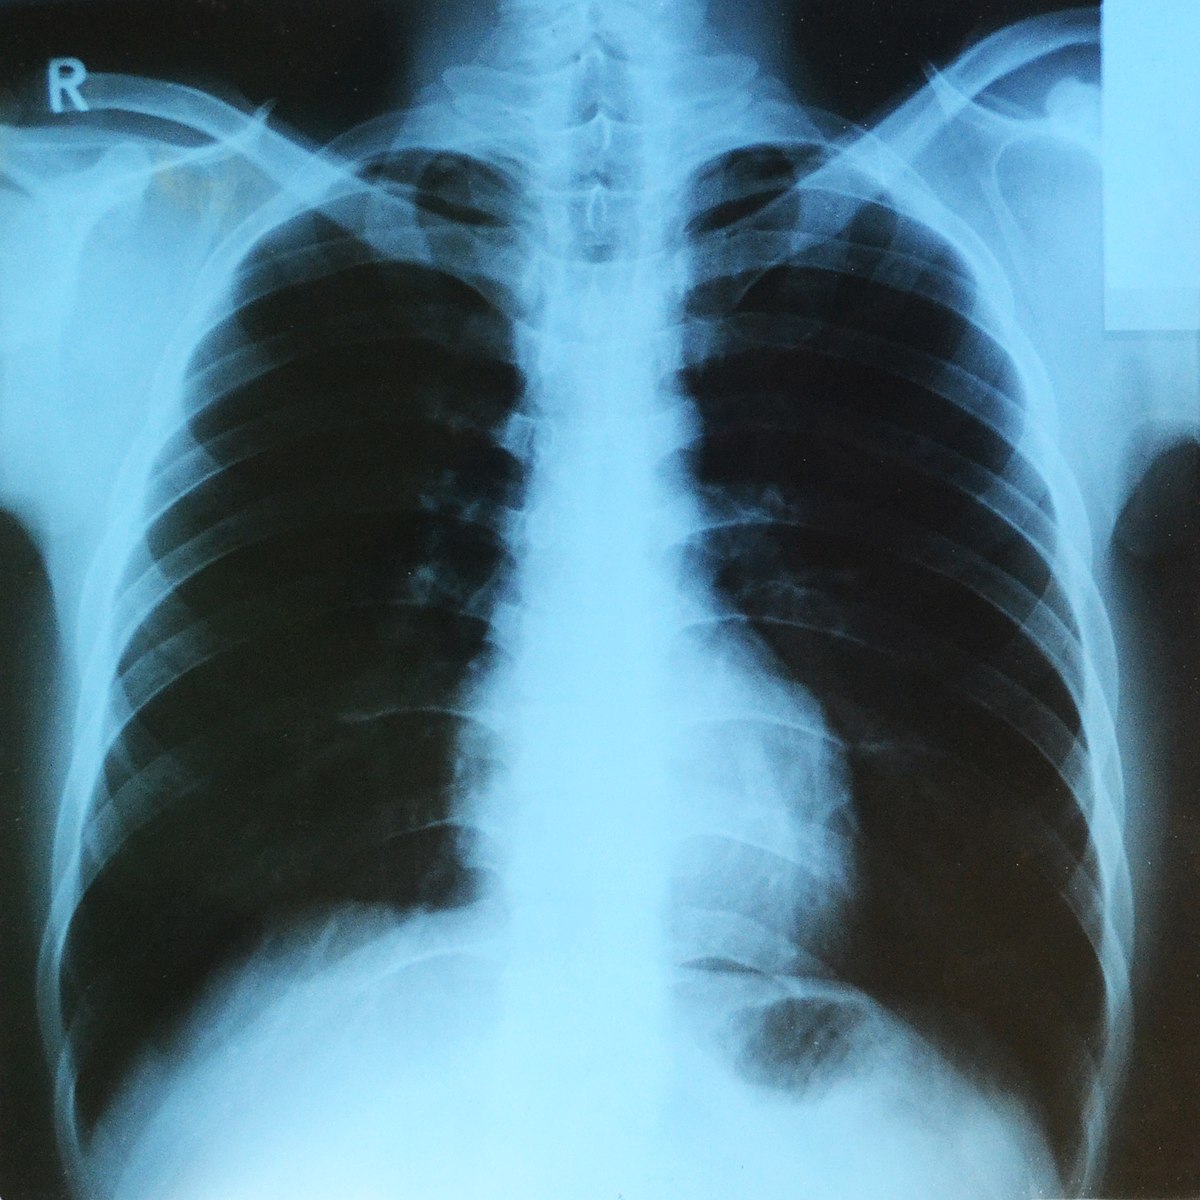

Millions of dollars are being spent to develop artificial intelligence software that reads x-rays and other medical scans in hopes it can spot things doctors look for but sometimes miss, such as lung cancers. A new study reports that these algorithms can also see something doctors don’t look for on such scans: a patient’s race.

Evidence that algorithms can read race from a person’s medical scans emerged from tests on five types of imagery used in radiology research, including chest and hand x-rays and mammograms. The images included patients who identified as Black, white, and Asian. For each type of scan, the researchers trained algorithms using images labeled with a patient’s self-reported race. Then they challenged the algorithms to predict...